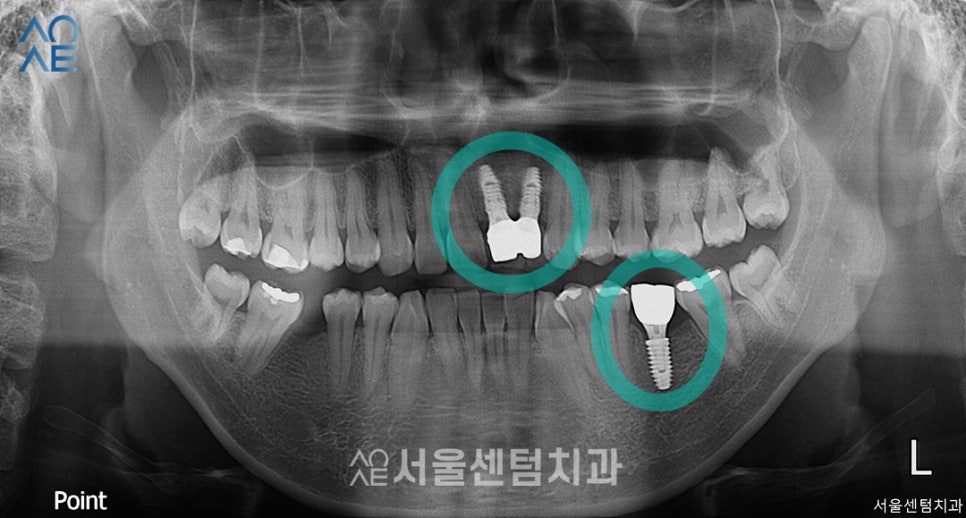

앞니 임플란트 포함하여 총 3개 수술을 마쳤습니다.

2차수술까지 진행하여

시간이 조금 걸렸지만

결과가 좋은 편이라 다행입니다.

보철물을 장착하기 위해서는

잇몸뼈와 픽스처의 융합이 잘 이뤄져야합니다.

융합이 이루어질 때까지 기다리는 동안

잇몸치료도 함께 진행하였고

임플란트 치료를 마무리하고 나서도

충치치료를 이어갔습니다.